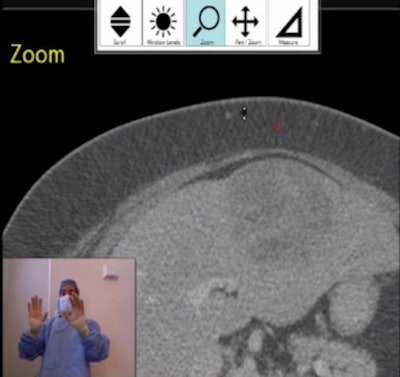

![]() |

| Screenshot shows third-year radiology resident Dr. Justin Tan demonstrating Kinect for intraoperative imaging review. The mouse cursor (red cursor) can be directed with gesture commands. In this case, Tan is using the zoom function to magnify the liver lesion. An enlarged toolbar is at the top of the display. All images courtesy of Dr. Cherng Chao. |